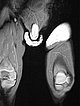

Die koronare, T2-gewichtete, fettgesättigte MRT zeigt den Tumor in der linken Leiste homogen stark hyperintens (13. Lebensmonat) und klar solide. Nebenbefundlich die durchnässte Windel, ebenfalls mit hoher Signalintensität.

Gleiche MRT-Sequenz, koronare Schichtführung. Der Tumor liegt nicht nur epifaszial, sondern zeigt auch eine geringe Ausdehnung nach subfaszial unter die Fascia lata in die Glutealmuskulatur. Damit klar infiltratives Verhalten.